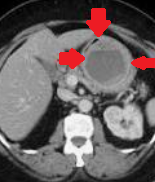

Red arrows – Rectal stromal tumor. Multiple liver metastases (Courtesy Dr. V. Penopoulos)